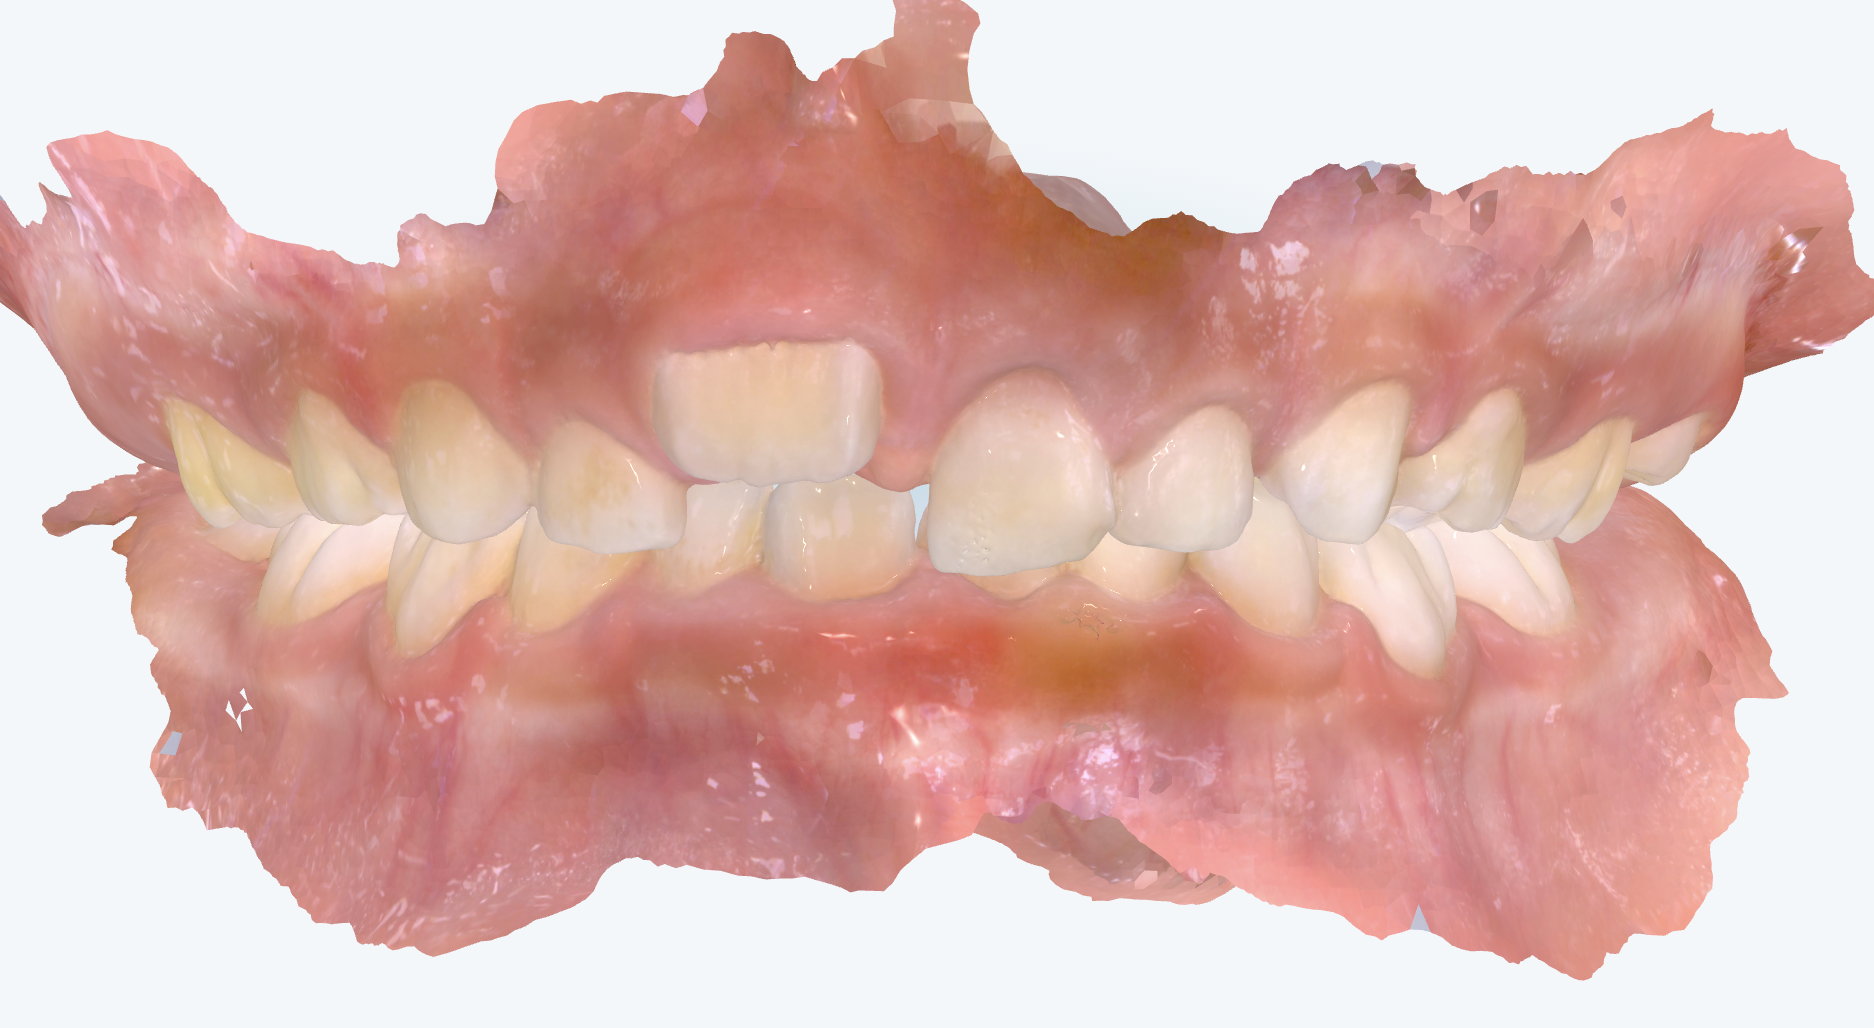

初診時の画像診断

上下の前歯の歯並びにガタガタがあります。

右上の前から1番目の歯が大きく前に出ています。